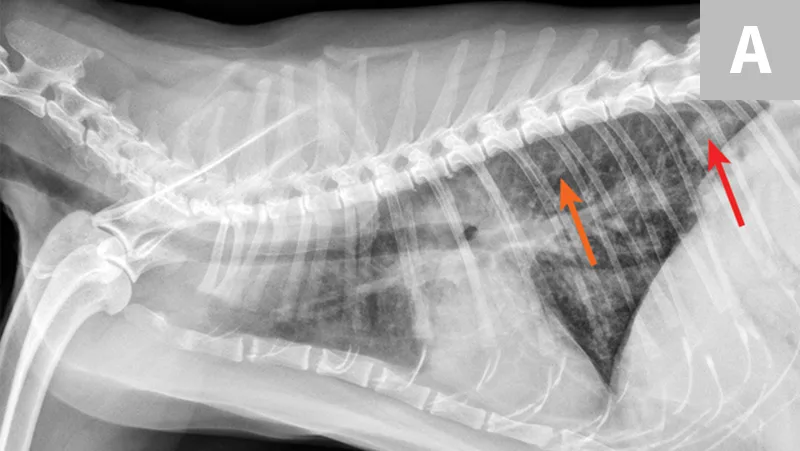

Overt cardiomegaly may be understated on radiographs because of changes in internal diameter that do not affect the overall cardiac silhouette. Vertebral heart score >9.3 supports a CHF diagnosis.1 Pulmonary venous congestion can be absent, and pulmonary arterial distension may be appreciated. The presence of pleural effusion with simultaneous pulmonary infiltrates is supportive of CHF (Figure 1).2

Congestive heart failure. Note the pleural effusion (arrows).